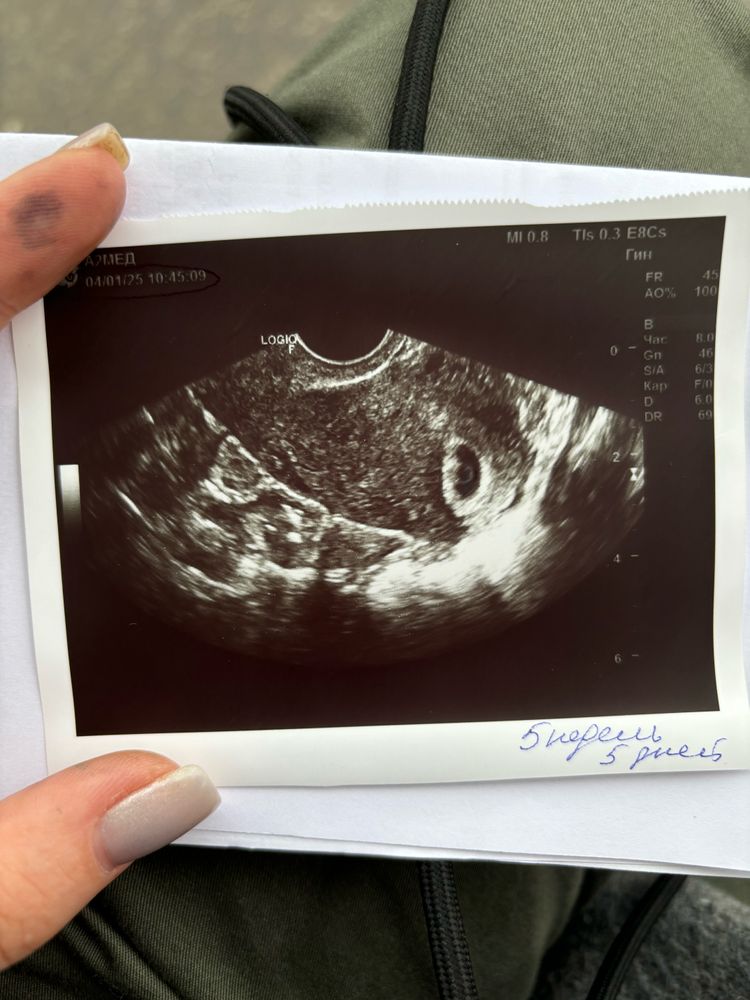

УЗИ 5н5д

Сегодня была на узи на сроке 5 недель 5 дней, по размерам пя срок совпадает.

форма и размер пя хорошие, эмбрион не визуализируется. Отправили домой ждать 10 дней и приходить повторно.

Смотрю у вас там в плодном яйце желточный мешок такой хороший) думаю все должно быть в порядке 🤞

ЖМ есть , пя по сроку ☺️

Думаю всё хорошо будет раз размеры пя соответствуют сроку, желточный мешочек виден тоже. Думаю на днях и эмбриончик появится. Я бы сходила раньше 10 дней, чтобы не накручивать себя в неизвестности) Дней через 5-6.